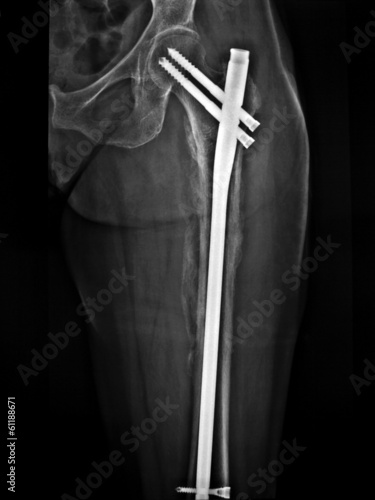

La frattura femore costituisce uno degli infortuni più comuni (soprattutto sotto capitata, localizzata al di sotto della testa sferica dell'osso. Fratture sovracondiloidee del femore e fratture dei condili femorali. Se la frattura si localizza subito al di sotto della testa sferica dell'osso è detta sotto capitata. Esercizi per il controllo dinamico del capo e del tronco in frattura del femore. Tipologie di frattura del femore. Caduta banalissima dalla mountain bike di domenica 27 gennaio 2013. La diagnosi di frattura di femore si ottiene con una semplice radiografia.larto appare accorciato ed extraruotato verso l'esterno.trattamenti diversi in base al tipo di frattura. Se viene identificata una frattura, devono essere eseguite le radiografie dell'intero femore. La fisioterapia per le fratture del femore. Menu principale il trattamento di una frattura del femore richiede quasi sempre l'intervento di sintesi chirurgica. Buongiorno dottore, il 3 di luglio durante l' allenamento in mtb, caddi rompendomi il collo del femore sx. Come si vede dalla radiografia, e vi metto anche una foto per paragone di come dovrebbe essere un femore sano, il femore sx di mia madre si è fratturato ed è scivolato fuori dall'acetabolo del bacino. Purtroppo è toccata anche a me la frattura del sotto capitato del femore sx. • frattura sottocapitata del femore; La tenue evidenza di frattura (p. Tipologie di frattura del femore. A maggio del 2006, a seguito di un banale incidente con la bici (un cane randagio è uscito all'improvviso da una cunetta e mi ha fatto cadere) ho avuto una frattura sottocapitata alla testa del femore.